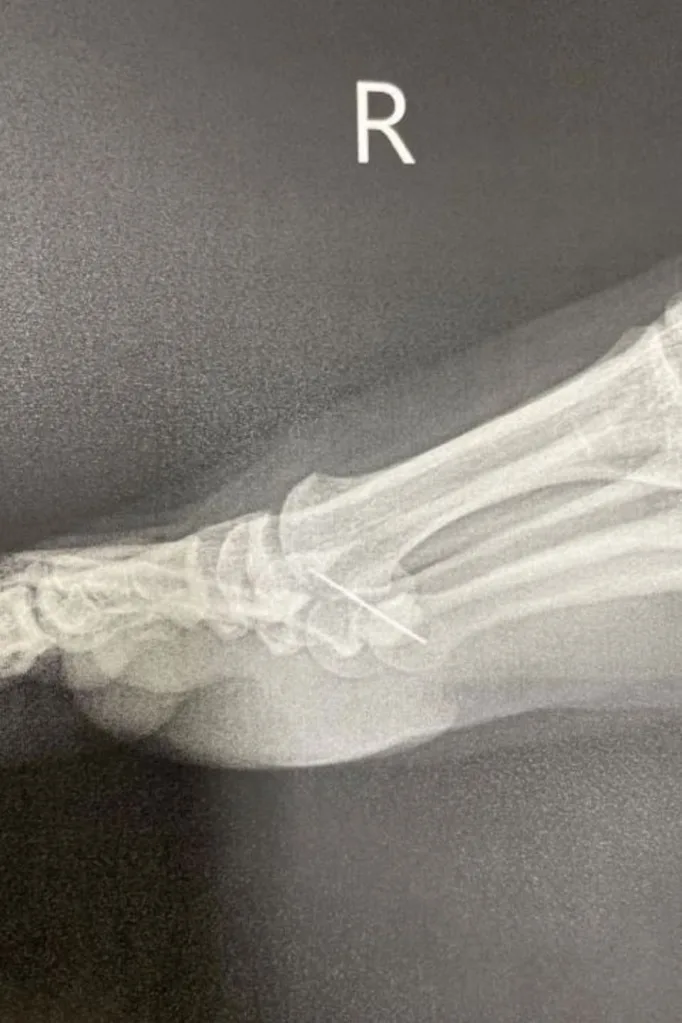

Despite having two-thirds of the needle into her foot, Turia waited a full day before going to the hospital.

“I was half expecting them to say ‘You silly sausage, it’s just a bruise’,” the motivational speaker wrote. “But instead they said, ‘Wow, it’s really deep’.”

Not only was the needle still in Turia’s foot, but it was also resting on a nerve amongst her bones to the point where the athlete required surgery.

“I had an operation to remove the needle and woke up feeling like my foot was on fire,” Turia added on her blog. “But each hour that passed after that, I got better and better. I needed less pain medication because I was getting better, my head fog cleared, and I was no longer thinking about the pain.”